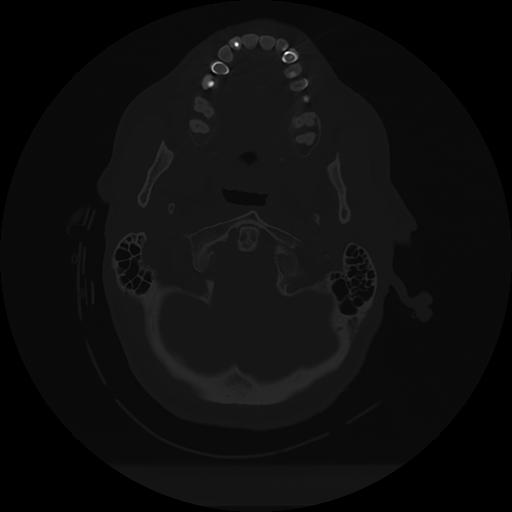

11 HUESO,,Axial,2.0,HUESO,,